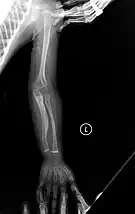

The main symptom of osteogenesis imperfecta is fragile, low mineral density bones; all types of OI have some bone involvement.[5] In moderate and especially severe OI, the long bones may be bowed, sometimes extremely so.[28] The weakness of the bones causes them to fracture easily—a study at the Endocrine Unit at the National Institute of Child Health in Karachi, Pakistan found an average of 5.8 fractures per year in untreated children.[29] Fractures typically occur much less after puberty, but begin to increase again in women after menopause and in men between the ages of 60 and 80.[1]: 486

- Type V – Having the same clinical features as type IV, it can be clinically distinguished by observing a "mesh-like" appearance to a bone biopsy under a microscope. Type V can be further distinguished from other types of OI by the "V triad": an opaque band (visible on X-ray) adjacent to the growth plates; hypertrophic calluses (abnormally large masses of bony repair tissue) which form at fracture sites during the healing process; and calcification of the interosseous membrane of the forearm,[50] which may make it difficult to turn the wrist.[1]: 429 Other features of this condition may include pulled elbow, and, as in other types of OI, long bone bowing and hearing loss.[64] Cases of this type are caused by mutations in the IFITM5 gene on chromosome 11p15.5.[64][49] The separation of type V from type IV OI, its clinical type, was initially suggested even before its genetic cause was known, by Glorieux et al. in 2000.[50][65] Type V is relatively common compared to other genetically defined types of OI—4% of OI patients at the genetics department of the Brazilian Hospital de Clínicas de Porto Alegre were found to have it.[66]

Diagnosis is typically based on medical imaging, including plain X-rays, and symptoms. In severe OI, signs on medical imaging include abnormalities in all extremities and in the spine.[97] As X-rays are often insensitive to the comparatively smaller bone density loss associated with type I OI, DEXA scans may be needed.[5]: 1514